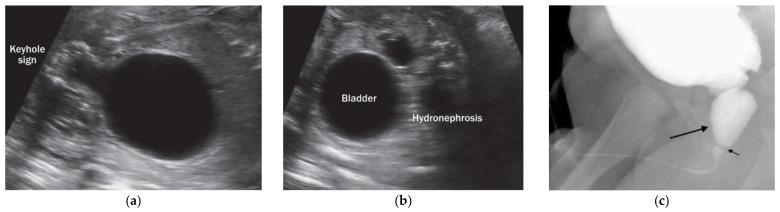

Lower urinary tract obstruction (LUTO) is, in most cases, caused by anatomical blockage of the bladder outlet. The most common form are posterior urethral valves (PUVs), a male-limited phenotype. Here, we surveyed the genome of 155 LUTO patients to identify disease-causing CNVs. Raw intensity data were collected for CNVs detected in LUTO patients and 4.392 healthy controls using CNVPartition, QuantiSNP and PennCNV. Overlapping CNVs between patients and controls were discarded. Additional filtering implicated CNV frequency in the database of genomic variants, gene content and final visual inspection detecting 37 ultra-rare CNVs. After, prioritization qPCR analysis confirmed 3 microduplications, all detected in PUV patients. One microduplication (5q23.2) occurred de novo in the two remaining microduplications found on chromosome 1p36.21 and 10q23.31. Parental DNA was not available for segregation analysis. All three duplications comprised 11 coding genes: four human specific lncRNA and one microRNA. Three coding genes (, , ) and the microRNA MIR107 have previously been shown to be expressed in the developing urinary tract of mouse embryos. We propose that duplications, rare or de novo, contribute to PUV formation, a male-limited phenotype.

下尿路梗阻(LUTO)在大多数情况下是由膀胱出口的解剖阻塞引起的。最常见的形式是后尿道瓣膜(PUV),这是一种男性特有的表型。在这里,我们对 155 名 LUTO 患者的基因组进行了调查,以确定致病的 CNV。使用 CNVPartition、QuantiSNP 和 PennCNV 为 LUTO 患者和 4392 名健康对照者检测到的 CNV 收集了原始强度数据。在患者和对照者之间重叠的 CNV 被丢弃。额外的过滤将 CNV 频率与基因组变异、基因内容和最终视觉检查数据库联系起来,检测到 37 个超罕见的 CNV。之后,通过 qPCR 分析对 3 个微重复进行了优先级排序,所有微重复均在 PUV 患者中检测到。一个微重复(5q23.2)在另外两个位于 1p36.21 和 10q23.31 染色体上的微重复中发生了从头突变。无法获得父母的 DNA 进行分离分析。所有三个重复都包含 11 个编码基因:四个人类特异性 lncRNA 和一个 microRNA。三个编码基因(、和)和 microRNA MIR107 之前已被证明在小鼠胚胎发育的泌尿道中表达。我们提出,重复,无论是罕见的还是从头发生的,都会导致 PUV 的形成,这是一种男性特有的表型。